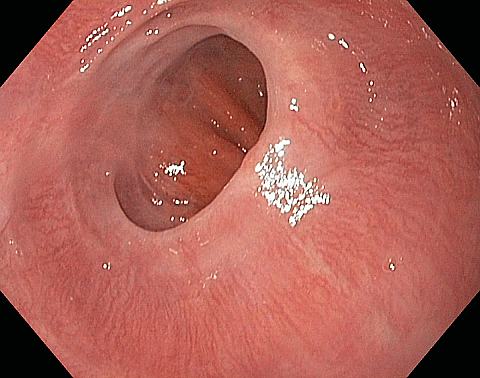

Reflux oesophagitis grade C-D according to the Los Angeles classification